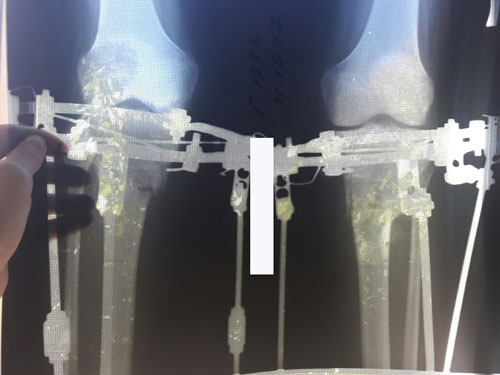

Дата операции 19.07.2017г

Дата снятия аппаратов 17.10.2017г.

Срок лечения 88 дней.

Только доктор Онипко может так красиво устранять Ротацию! Браво ему!!!